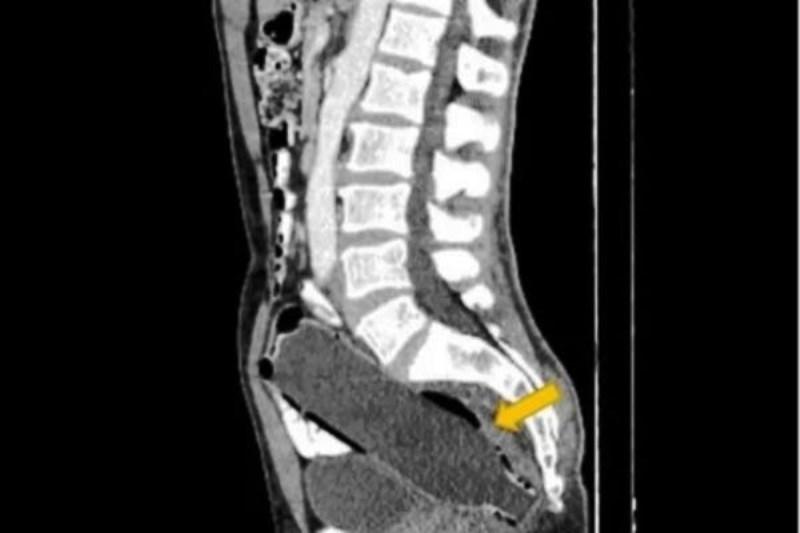

Médicos encontram garrafa de água de 250ml introduzida no reto de iranianoGarrafa plástica de 250ml introduzida no reto do iraniano – Foto: Reprodução/Clinical Case Reports

Um homem iraniano de 50 anos foi levado ao hospital pela mulher depois de relatar falta de apetite, dores no estômago e constipação – também conhecida como intestino preso. O paciente foi submetido a uma tomografia computadorizada, que revelou o motivo do desconforto: uma garrafa plástica de 250ml introduzida no reto. O caso foi publicado na revista Clinical Case Reports na última quinta-feira (14).

O objeto de 19 cm foi encontrado na região pélvica do paciente, a 10 milímetros da abertura do ânus, e estava alocada entre o reto e o cólon, que faz parte do intestino grosso. De acordo com a revista, o homem introduziu primeiro o fundo da garrafa, na intenção de retirá-la segurando a tampa. No entanto ele não conseguiu extrair o item deixando a garrafa plástica alojada no reto.